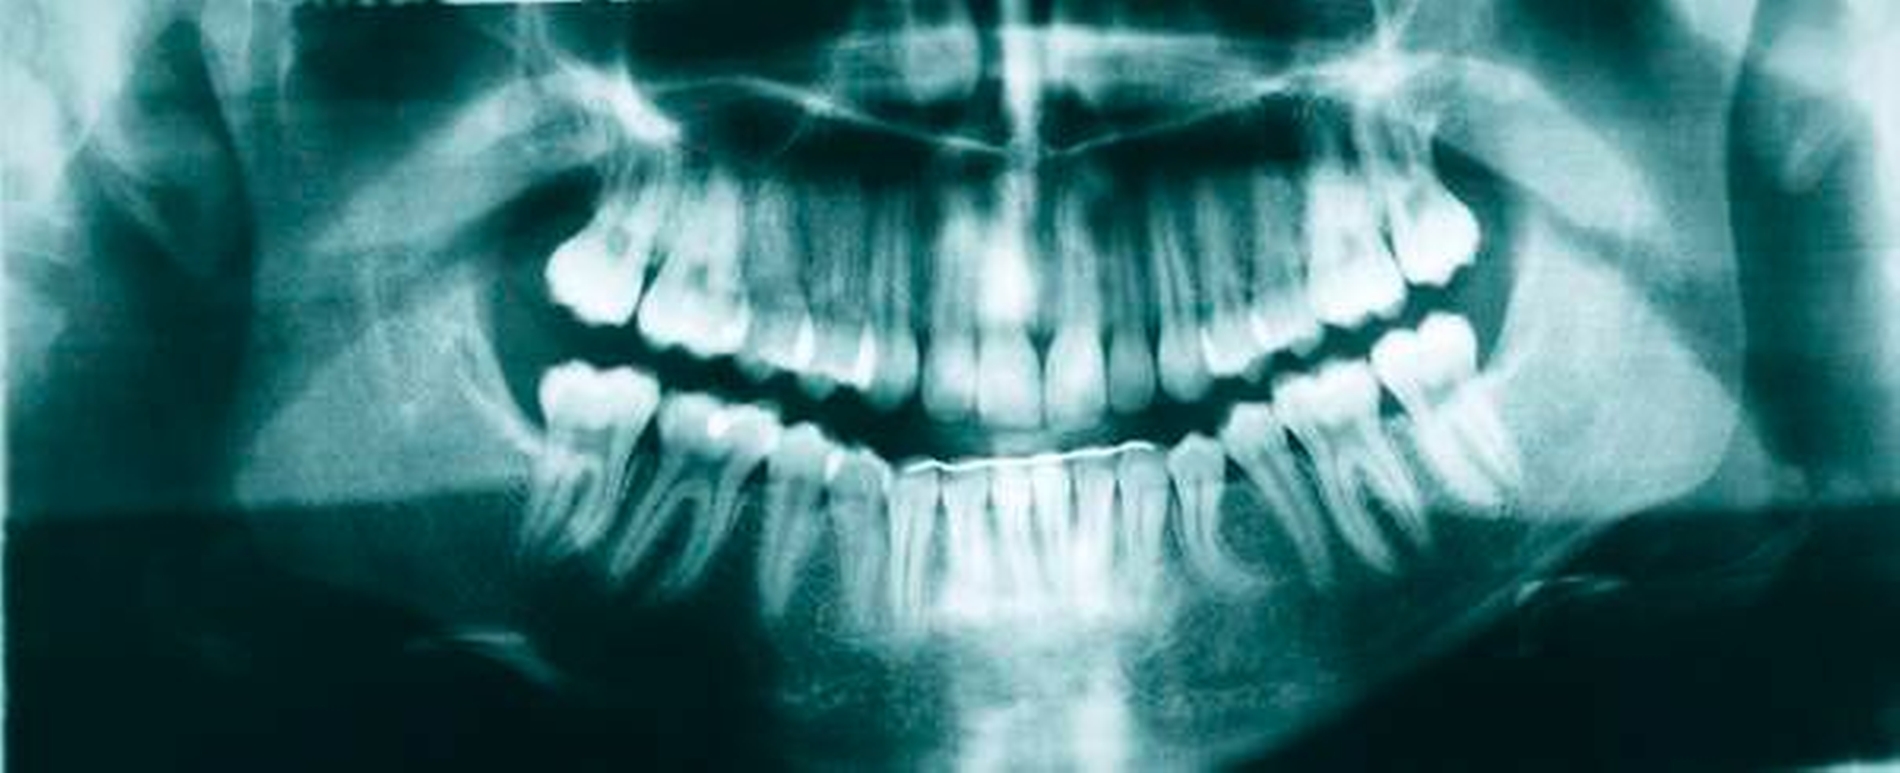

Im Orthopantomogramm imponierte eine Aufhellung, die sich regio 33 bis 35 nahezu über die gesamte vertikale Dimension des Unterkiefers erstreckte und die Krone des Zahnes 34 einschloss. Dieser lag horizontal verlagert, die Krone nach distal orientiert über die Wurzeln der Zähne 41 bis 74 projiziert. Zudem konnten die Anlagen der vier Weisheitszähne mit drohendem Engstand sowie ein nach mesial angulierter Zahn 24 befundet werden (Abbildung 4).

Im abschließenden OPG war der Zahn 34 regelgerecht eingeordnet, die nach distal deviante Wurzelspitze ist aller Wahrscheinlichkeit nach der Verlagerung geschuldet (Abbildung 8).